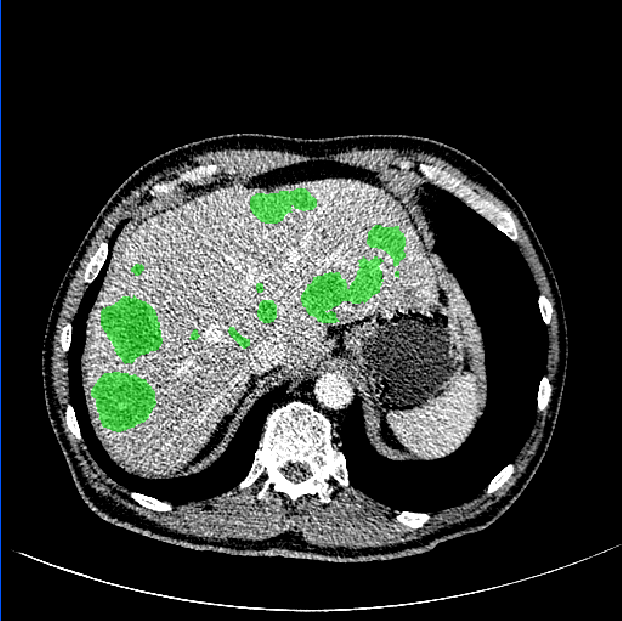

3.1 Comparison of Various Distance Maps Regression

A simple illustration of distance maps is shown in Fig. 2, which contains the binary segmentation mask, O-DM, inverse distance map (I-DM), NI-DM and sign norm inverse distance map (SNI-DM). I-DM is derived from the I-DM by taking inverse operation. SNI-DM is modified from the NI-DM, where the voxel inside the boundary of the target object is positive, otherwise is negative.

As shown in Fig. 3, our method demonstrates superior qualitative results, especially in the notoriously small tumors segmentation. In Table 1, the results show that the M-Net with the LR-Net achieves better performance than M-Net alone on all the evaluation criteria. This indicates indicates the significance of LR-Net on accuracy improvement. Then, we evaluate the performance of MapDice loss. By comparing the results with and without the MapDice loss, it is apparent that MapDice loss contributes a lot for segmentation accuracy improvement. In particular, the MapDice loss yields the superior results of NI-DM regression, while Dice loss shows a significant drop in the last four columns of Table 1. This indicates that distance map can help the network to capture semantically meaningful regions and produce more accurate reslults. The constant value , used to balance the magnitude difference of two different losses, is also verified to be effective for the performance improvement.